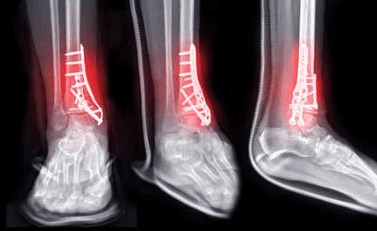

이번에도 무시했던 퇴원비 기다리다가 찾아보니 제일 많이 나오는듯.. 물론 다 이유가 있는듯. 전에. 그는 그것을 확인했다. 이 말을 듣고 또 겁이 나서 사진을 찍었다고 한다. 안전하지 않은 혼합물이 포함되어 있습니다. 이들 중 가장 큰 것은 인공 골분과 같은 것입니다. 의사선생님 말씀에 처음에 넣었다가 동의서에 싸인하고 보니 저렴한 비보험 서비스인줄 알았어요 MRI, 인조골분, 비급여약값 빼면 , 100만 원을 추가로 절약할 수 있었습니다. , 실제 비용 덕분에 정말 운이 좋았습니다. 이번 2건의 수술은 기존에 납부했던 실비를 소진한 것으로 보입니다(참고로 2016년 등록 실비입니다). 또 이번에는 배제가 커서 또 입원 신고가 들어와 모두 접수됐다. 어쨌든 내가 할 수 있고 다리 건강을 유지하는 한 그것은 낭비가 아닙니다. 건강은 무조건 중요하고 중요합니다.

삼각골절정판제거/ 삼각골절정판제거+허리통증 #삼각대골절정술 #삼각대골절정술 #삼트릭스골절정술 #삼트릭스골절정정술 #삼각절단술 … m .blog.naver.com